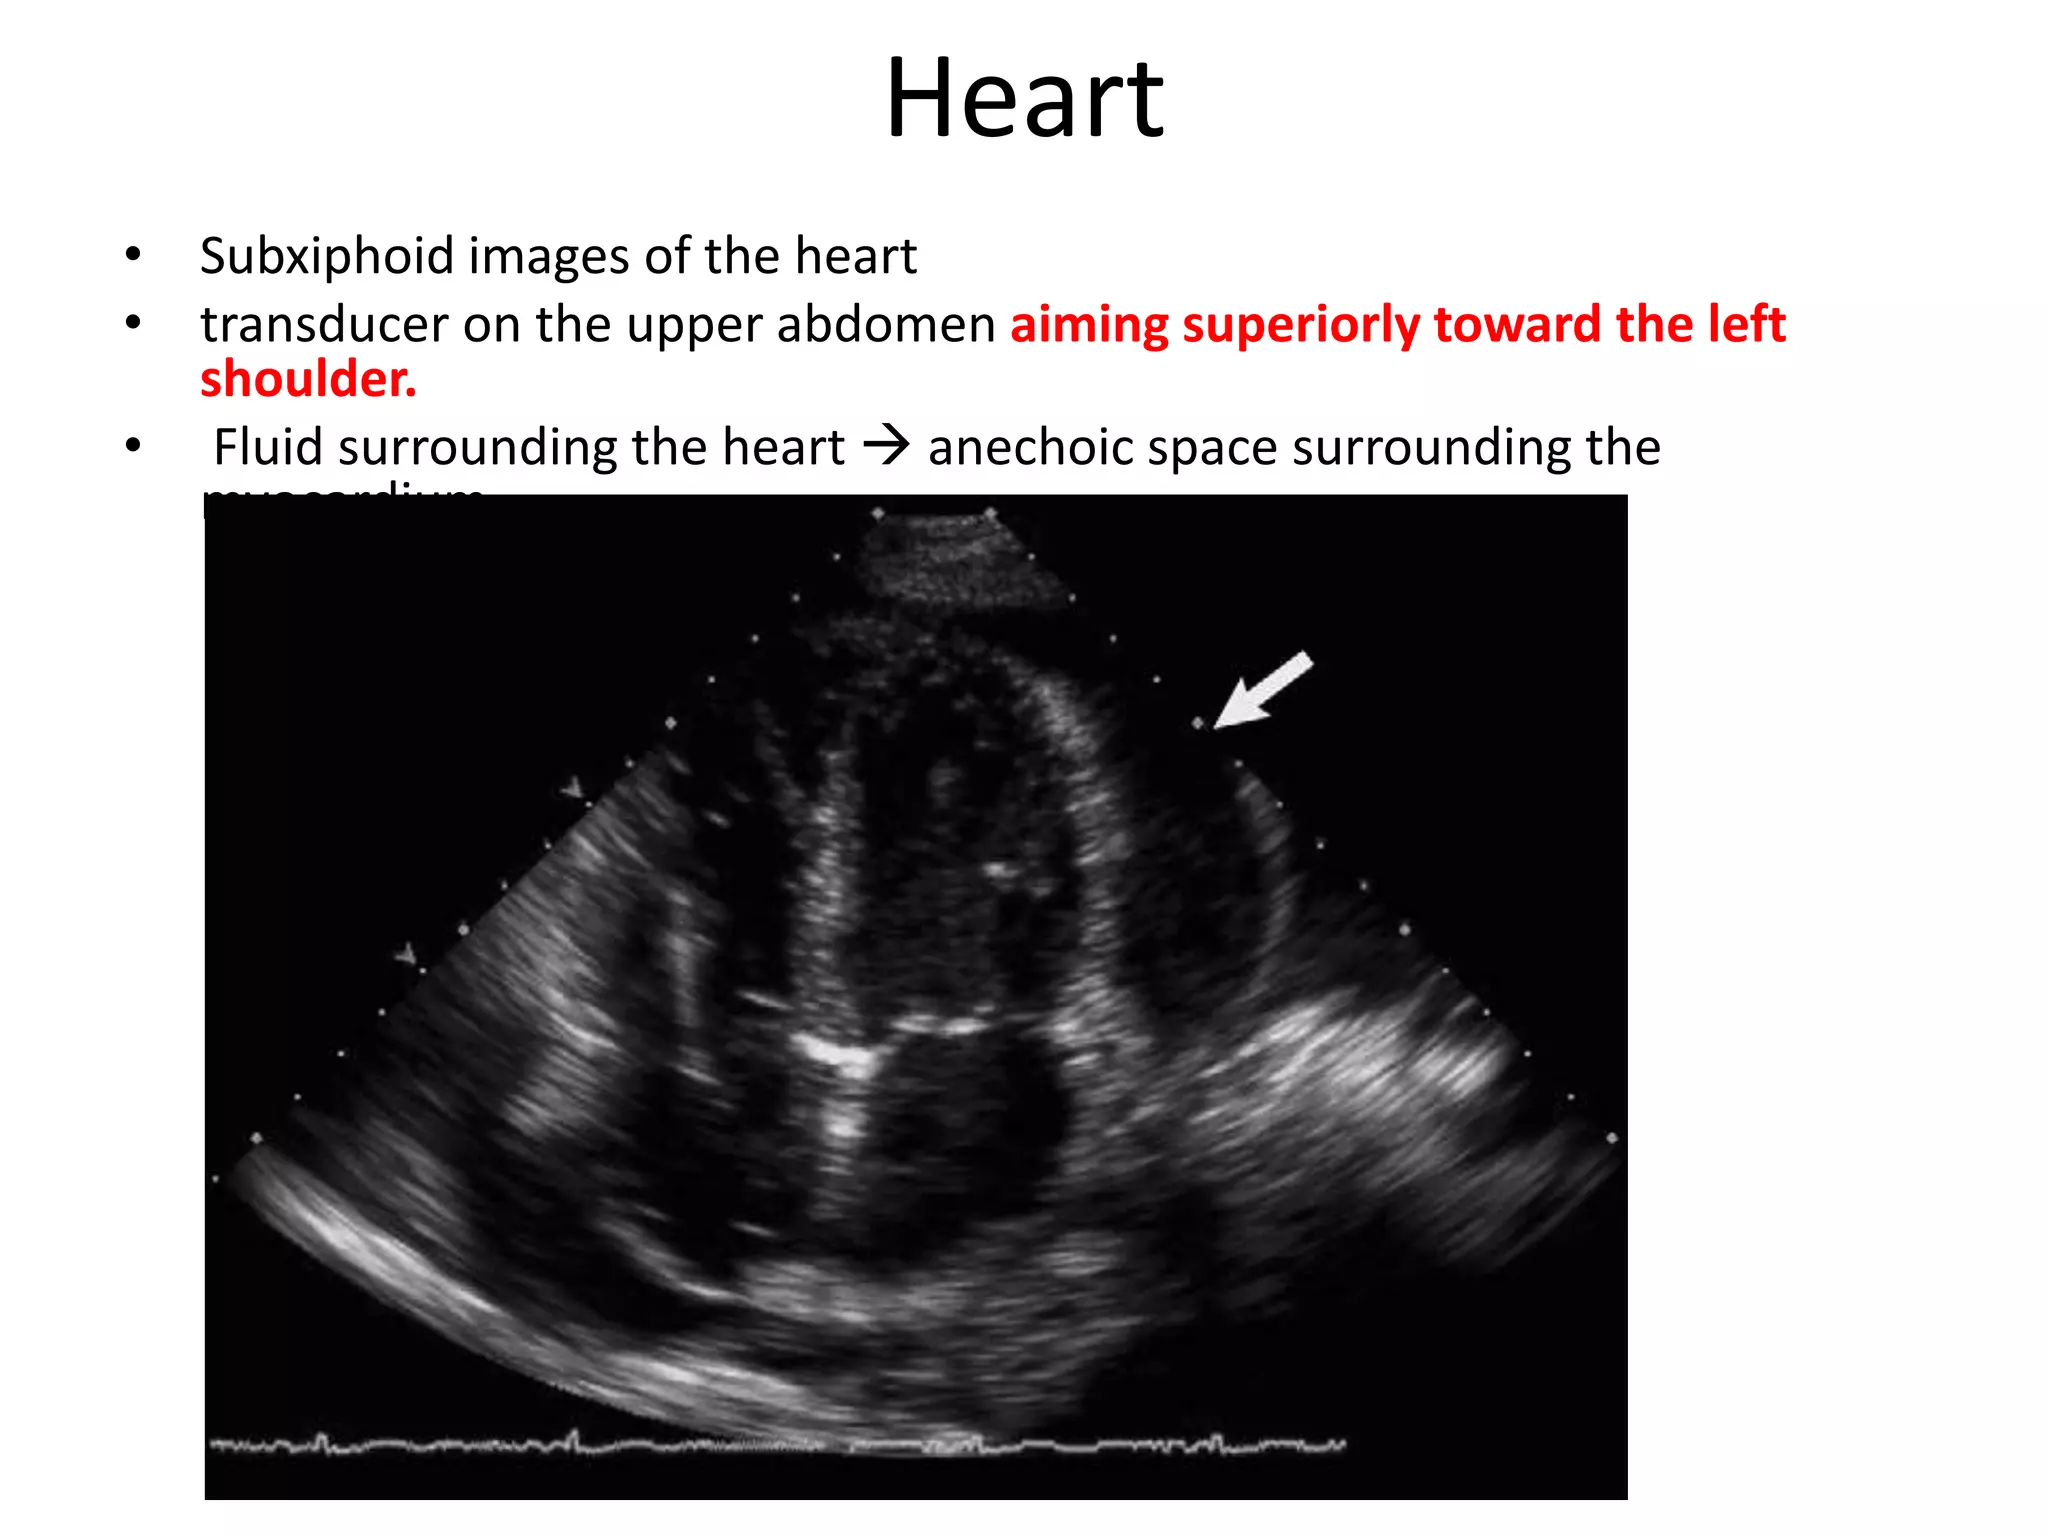

Heart

• Subxiphoid images of the heart

• transducer on the upper abdomen aiming superiorly toward the left

shoulder.

• Fluid surrounding the heart  anechoic space surrounding the

myocardium